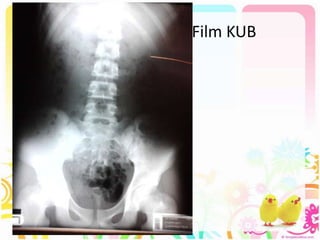

Film KUB